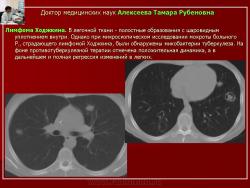

Следует отметить, что не всегда при туберкулезе легких отмечалась классическая скиологическая картина. Трудности в постановке диагноза туберкулеза возникали при появлении множественных полостных образований в легких с тонкими стенками на фоне неизмененной легочной ткани. В отдельных полостях определялись шаровидные массы, что заставило расценить выявленные в легких изменения как проявления аспергиллеза (рис. 7).

Рис. 7. Б-ного Р. Лимфома Ходжкина. В легочной ткани - полостные образования с шаровидным уплотнением внутри.

Однако при микроскопическом исследовании мокроты больного Р., страдающего лимфомой Ходжкина, были обнаружены микобактерии туберкулеза. На фоне противотуберкулезной терапии отмечена положительная динамика, а в дальнейшем и полная регрессия изменений в легких.